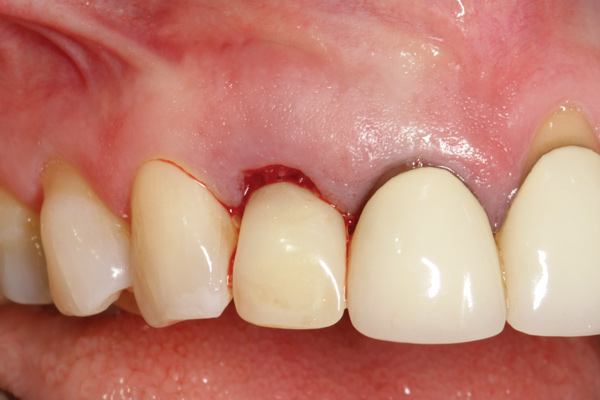

Fig 1. Clinical photograph showing significant issues related to implant midfacial mucosal recession and loss of interdental papillae. This is attributed to incorrect implant positioning (too buccal and too deep); several corrective surgeries resulted in interproximal bone loss, then loss of interdental papillae.

Figure 1

A minimum of 2 mm of facial bone thickness has been proposed as the “critical bone thickness” for the prevention of vertical height loss of the facial plate. It has been reported that when the distance of the buccal shoulder position of the implant to facial bone plate is below this critical thickness, an increased amount of facial bone resorption may be observed, which, in turn, may increase the chance of implant mucosal recession and failure (Figure 1). When the facial bone thickness is more than 2 mm from the implant buccal shoulder position, the likelihood of facial bone loss is decreased and the chance for alveolar bone stability is, therefore, increased.16

Chen and coworkers evaluated the soft-tissue and radiographic outcomes of implants placed in extraction sockets using a nonsubmerged protocol. The result showed statistically significantly higher marginal tissue recession at sites when implants were placed 1.1 mm from the inner buccal socket wall compared with implants placed 2.3 mm from the inner buccal socket wall. Six of the eight implant cases that were buccally positioned had unsatisfactory post-restorative esthetic outcomes. The authors concluded that position of the implant shoulder within the socket is a critical factor for ideal esthetic outcomes; thus, a minimum of 2 mm distance from the implant shoulder to the inner buccal shoulder wall was recommended to prevent implant marginal tissue recession.5